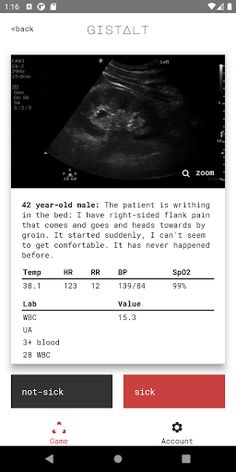

Your goal playing gistalt is to accurately identify which patients are sick (requiring hospitalization or immediate interventions for stabilization) or not-sick (conditions that can be safely treated with outpatient follow-up).

gistalt games are simple and fun. You'll start with a stack of patient presentations including vital signs, laboratory results and imaging. Swipe each card left (for not-sick) or right (for-sick) to see the next question. At the end of the stack, review your responses and see your score. Your gistalt score specially gauges your ability to detect the most critically-ill patients and institute the treatments that will make a difference.